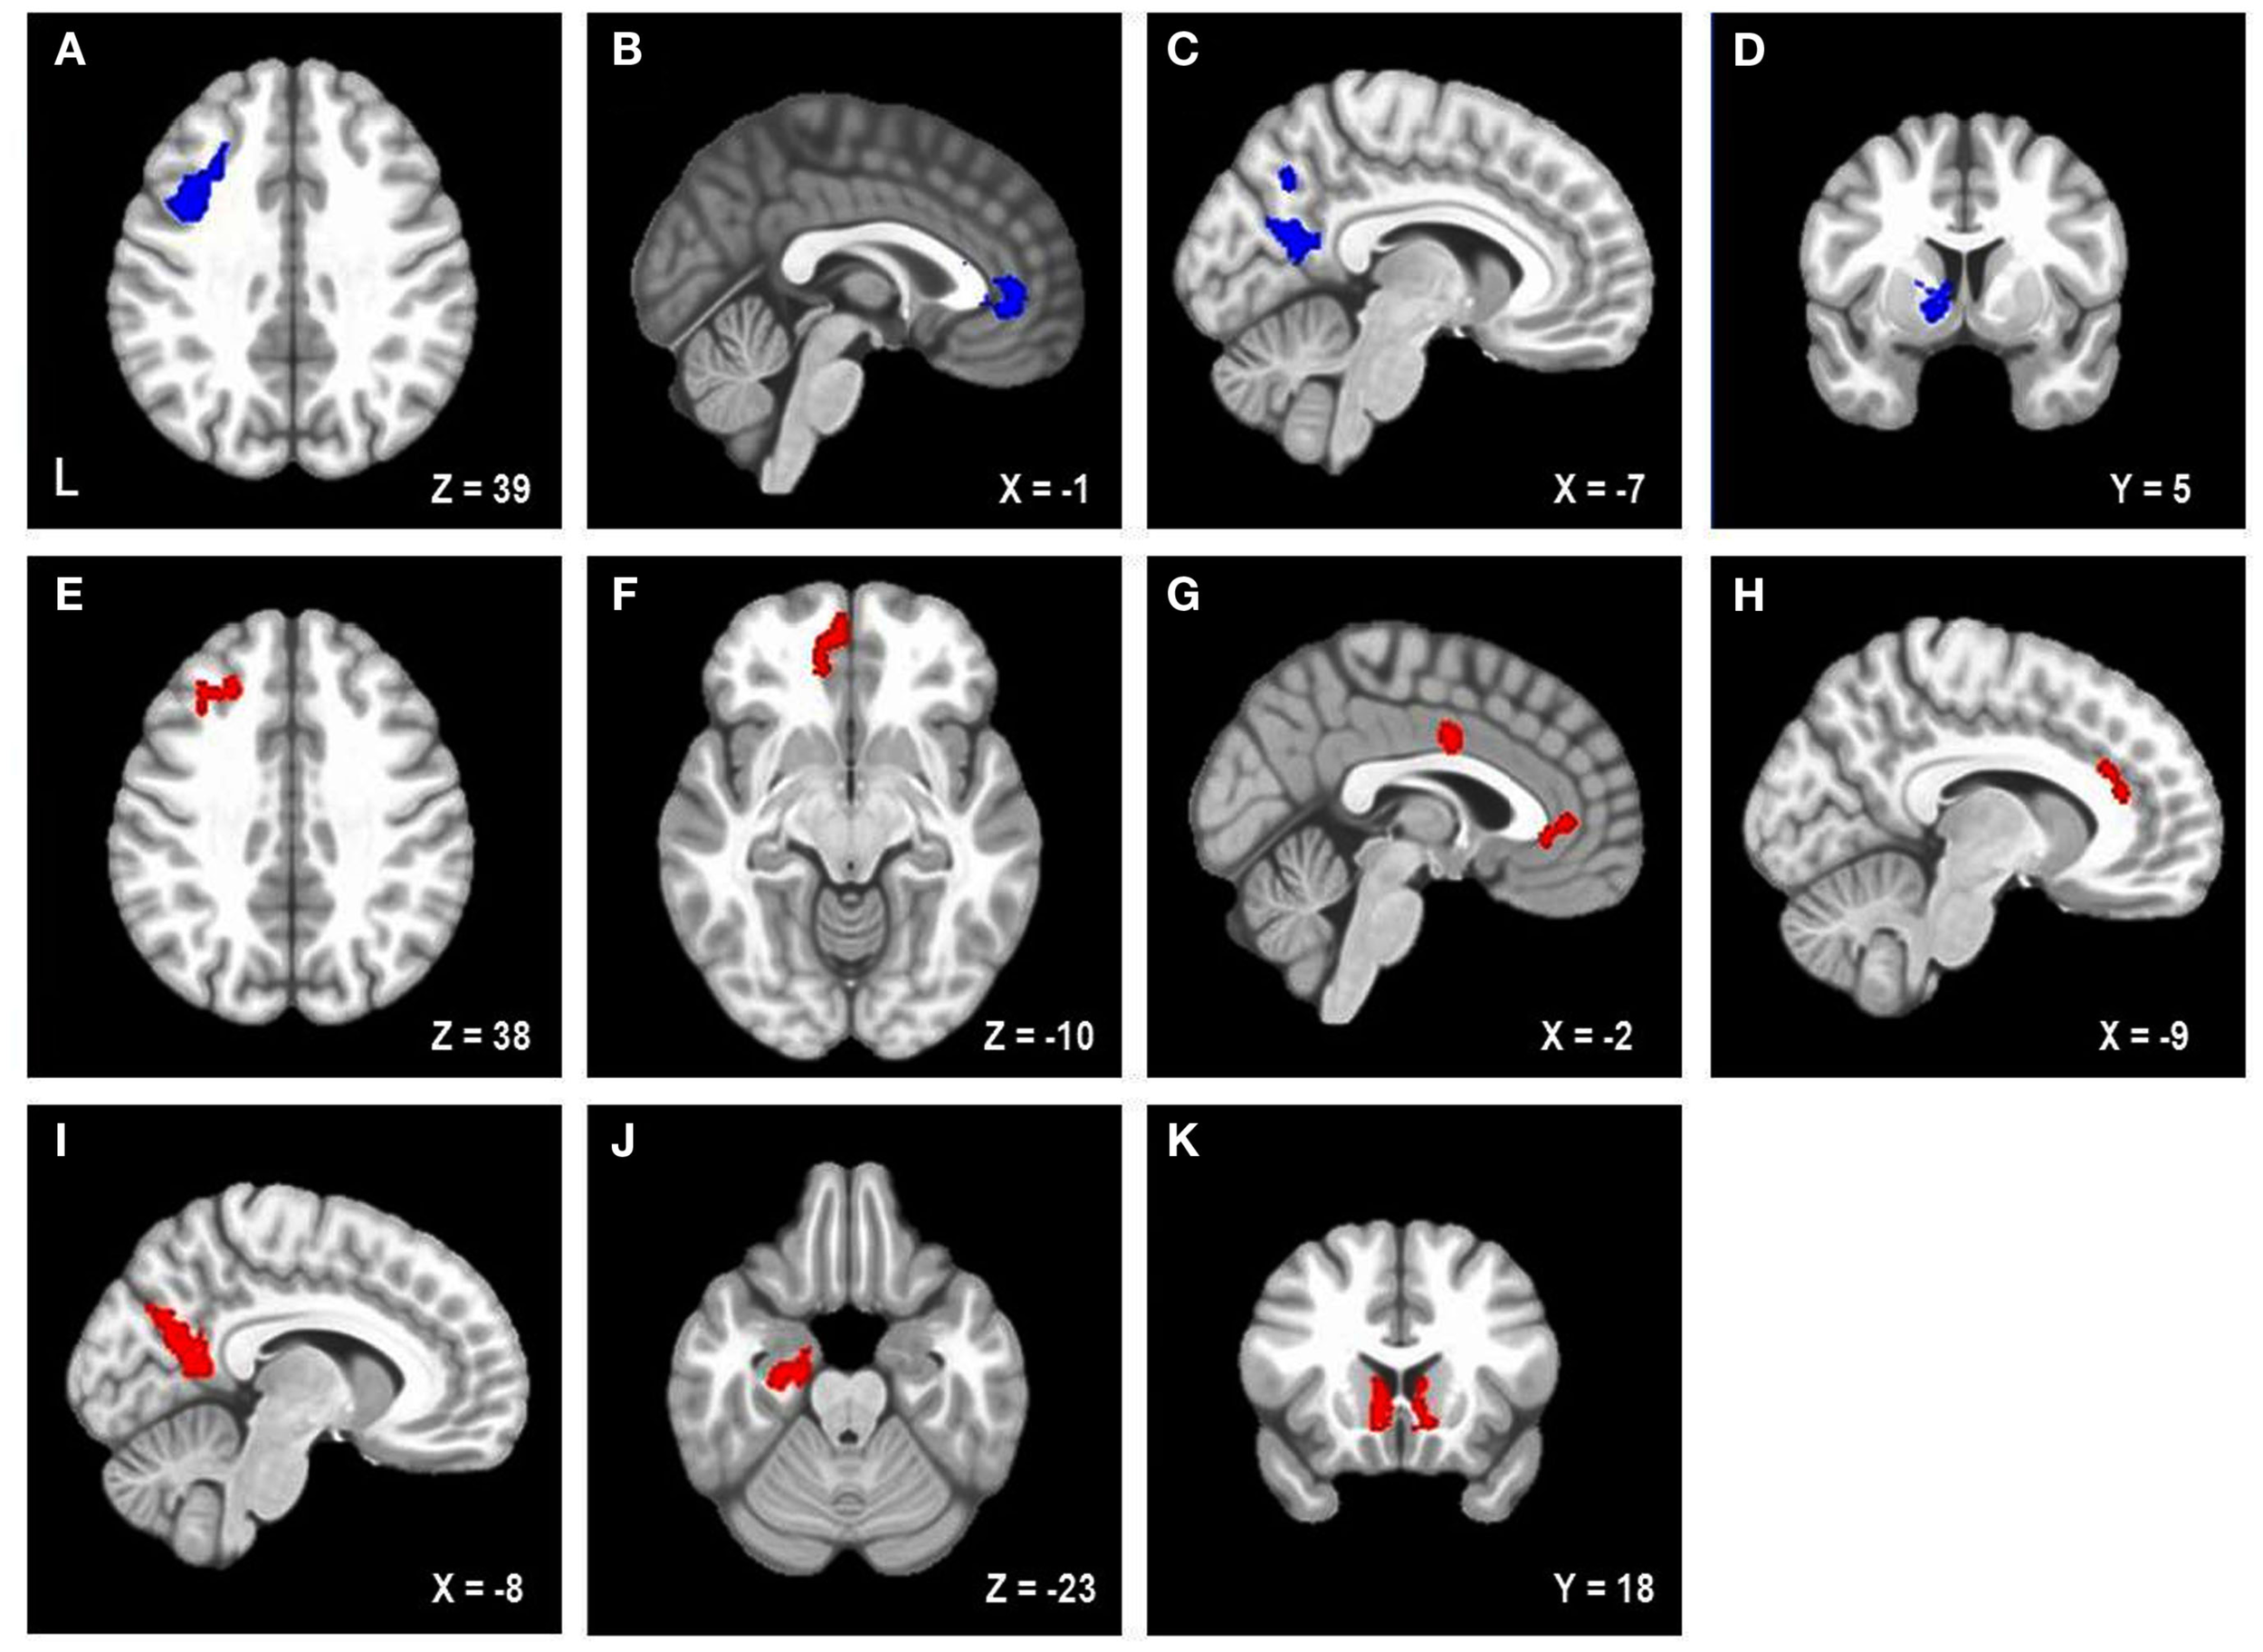

Table 2 lists the four brain regions that were negatively correlated with trait NA. In line with hypotheses, higher levels of trait NA were associated with less brain activation in left posterior DFPFC [middle frontal gyrus (MFG) extending into precentral gyrus], rACC, and precuneus (see Figure 1). In addition, a cluster emerged in left caudate when using the whole-brain gray-matter mask. There were no significant amygdala clusters. Further, there were no significant clusters positively correlated with trait NA. An examination of the valence contrast (negative vs. positive words) confirmed that there were no significant activations overlapping with any of these four areas, indicating that these results were not driven by negative or positive words alone.

Figure 1

Areas uniquely associated with either trait or state negative affect (NA). Blue = decreased brain activation associated with trait NA (A–D). Red = increased brain activation associated with state NA (E–K). L, left. Clusters of activation in (A) Left posterior DLPFC, (B) Rostral anterior cingulate cortex (rACC), (C) Precuneus, (D) Left caudate, (E) Left mid-DLPFC, (F) Left medial frontal cortex, (G) rACC and posterior dorsal ACC (dACC), (H) dACC, (I) Precuneus, (J) Parahippocampal gyrus, (K) Bilateral nucleus accumbens/caudate.

Brain regions uniquely associated with state negative affect

Table 2 lists the regions that were positively correlated with state NA. In line with hypotheses, higher levels of state NA were associated with more activation in mid-DLPFC [MFG, extending into inferior frontal gyrus (IFG)], ACC, and precuneus (see Figure 1). Three separate clusters emerged in the ACC: rACC, an anterior region of dorsal ACC (dACC), and posterior dACC. In addition to mid-DLPFC, a second cluster emerged using the frontal cortex mask, in left medial frontal cortex. Finally, when using the whole-brain gray-matter mask, two additional clusters emerged: one in left parahippocampal gyrus and one spanning left and right nucleus accumbens/caudate. There were no significant amygdala clusters. Further, there were no significant clusters negatively correlated with state NA. An examination of the valence contrast (negative vs. positive words) confirmed that there were no significant activations overlapping with any of these eight areas.